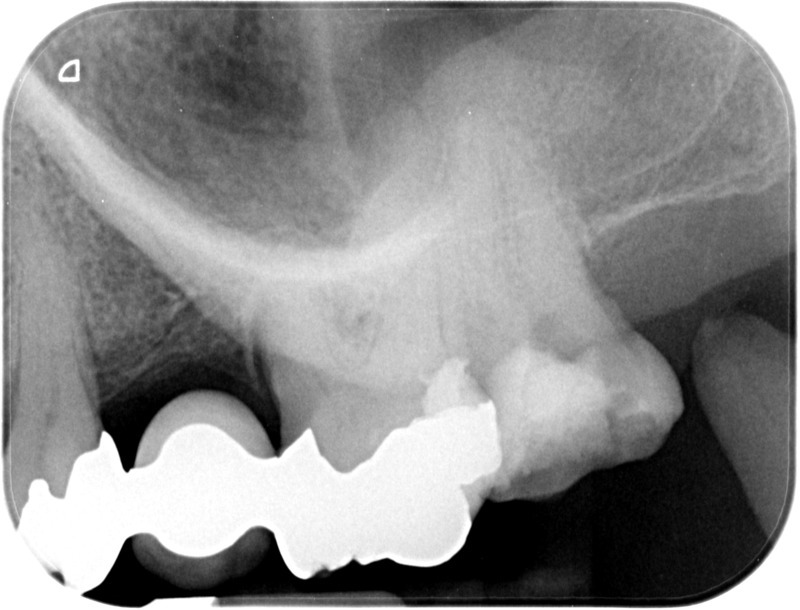

• Reprise de traitement endodontique : La manœuvre consiste à retourner à l’intérieur des racines d’une dent déjà traitée. Il arrive occasionnellement qu’une nouvelle inflammation se déclare suite à une reprise de carie ou une fracture de la dent, ou si le premier traitement endodontique est incomplet. Après s’être assuré que la dent lésée était conservable, il convient de désinfecter de nouveau le réseau canalaire parfois très complexe. La nouvelle obturation des canaux devra être protégée aussi rapidement que possible pour éviter une éventuelle contamination bactérienne.

Avant

Après